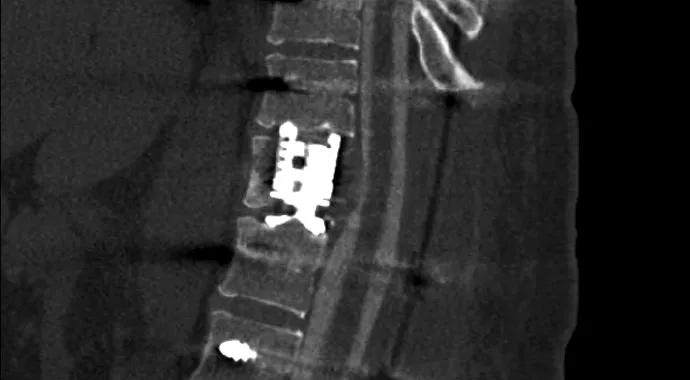

The surgery was performed at Cleveland Clinic’s Fairview Hospital, where the patient worked with a team of therapists to expedite her mobility and recovery and went home to continue outpatient physical therapy. With the spinal cord decompressed (Figure 3) and her mechanical back pain significantly improved, she was ready for the next steps of treatment.

Perry-Angelov-Fig3

Figure 3. Postoperative CT myelogram demonstrating decompression of the spinal cord.